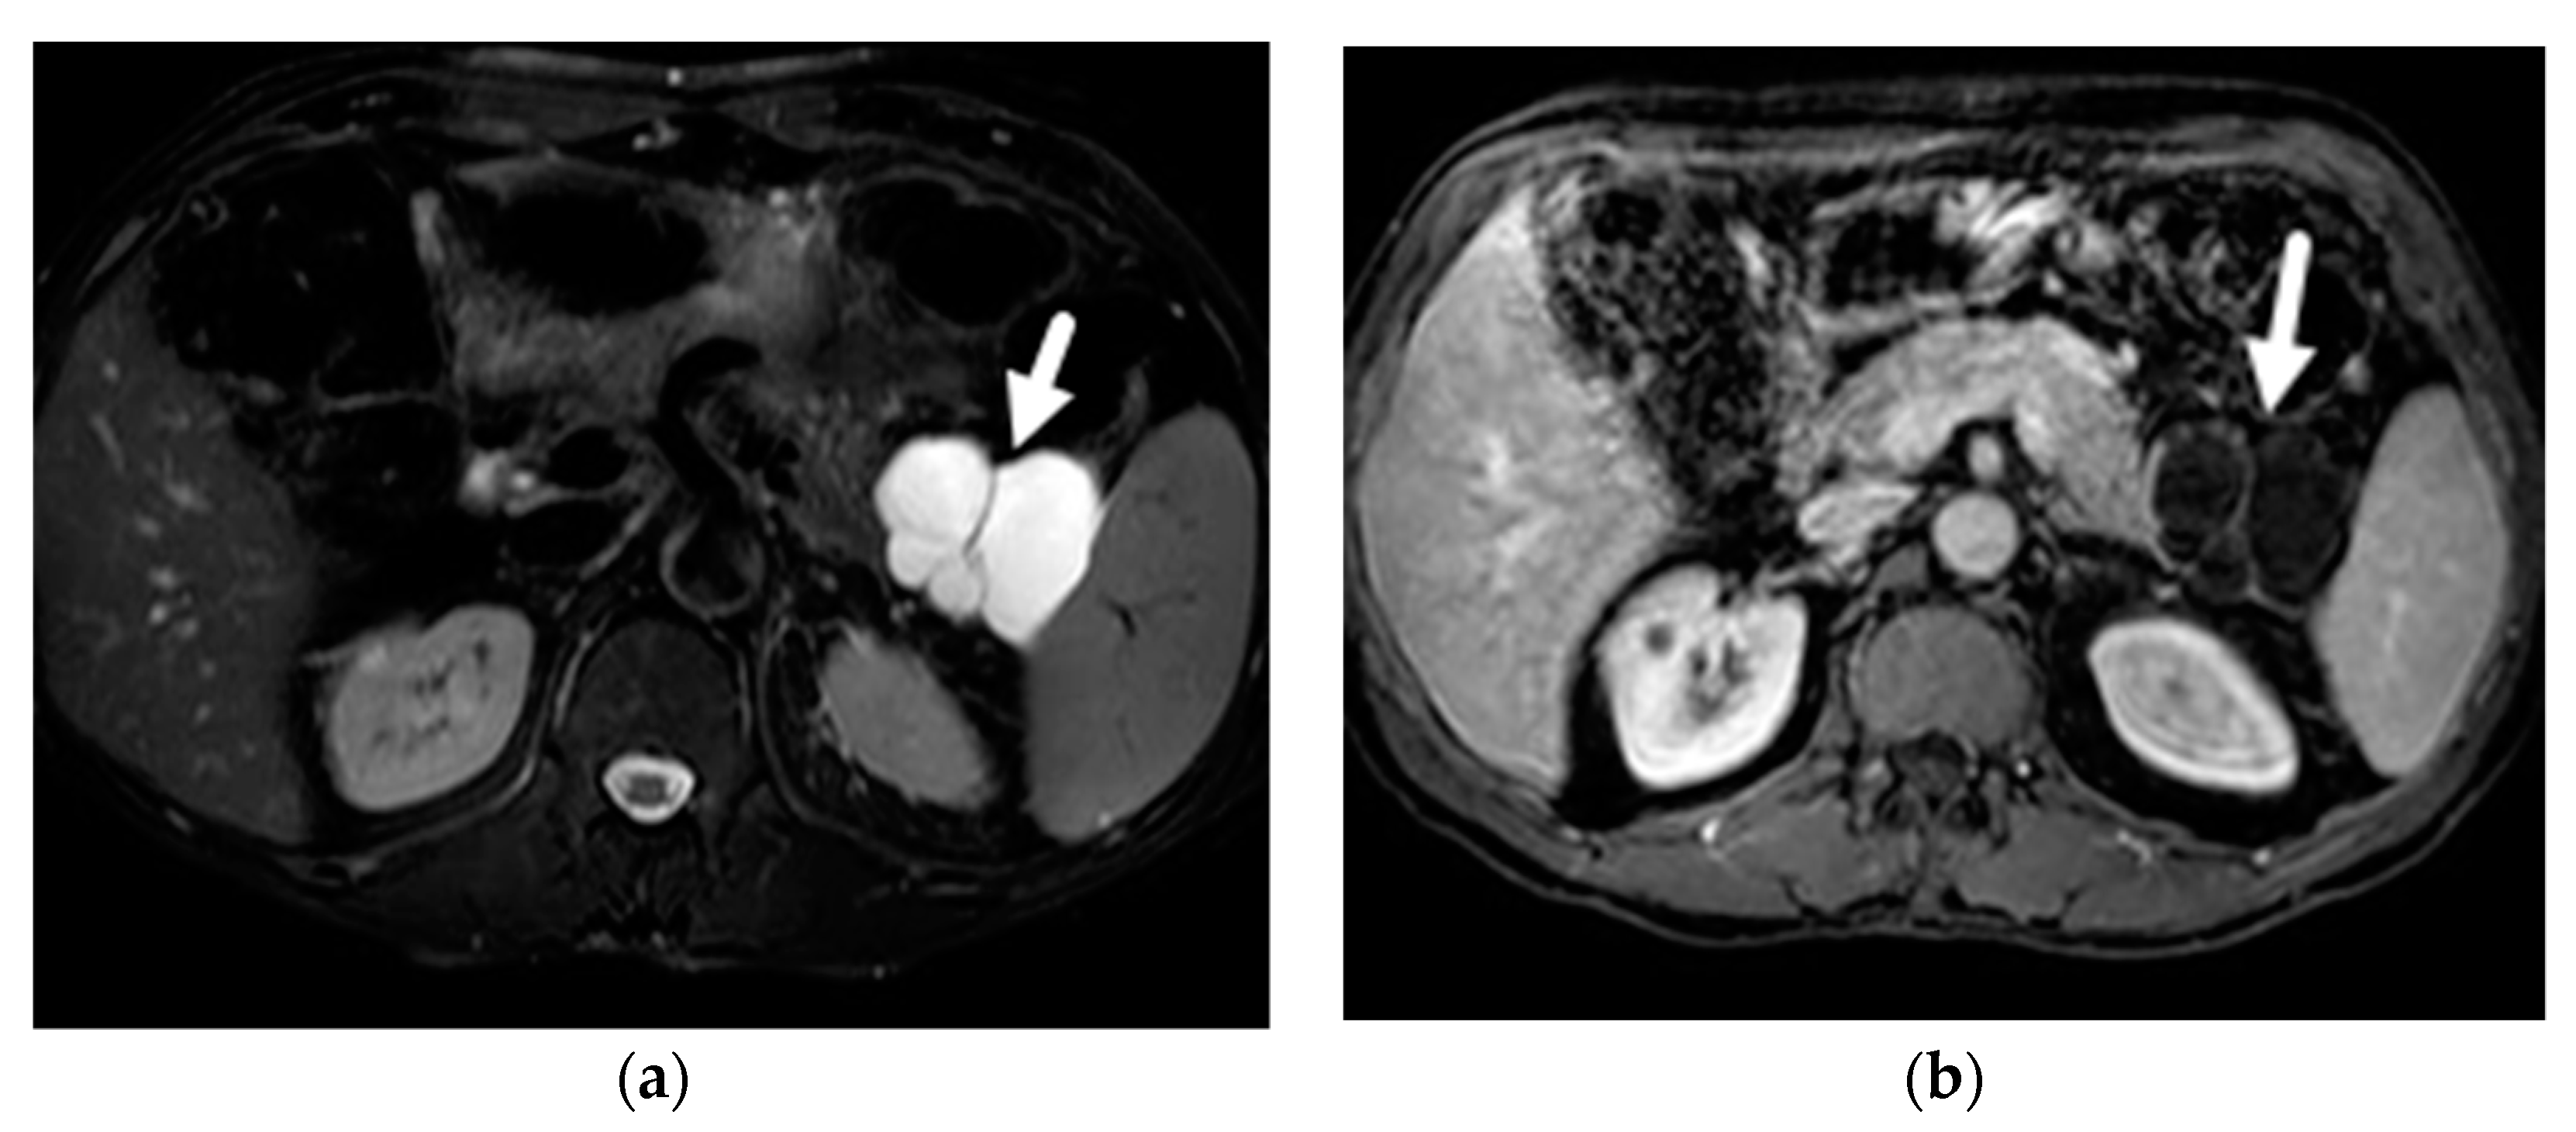

- Mamone, G.; Barresi, L.; Tropea, A.; Di Piazza, A.; Miraglia, R. MRI of mucinous pancreatic cystic lesions: A new updated morphological approach for the differential diagnosis. Updates Surg. 2020, 72, 617–637. [Google Scholar] [CrossRef] [PubMed]

- Garces-Descovich, A.; Beker, K.; Castillo-Angeles, M.; Brook, A.; Resnick, E.; Shinagare, S.; Najarian, R.M.; Mortele, K.J. Mucinous cystic neoplasms of the pancreas: High-resolution cross-sectional imaging features with clinico-pathologic correlation. Abdom. Radiol. 2018, 43, 1413–1422. [Google Scholar] [CrossRef]